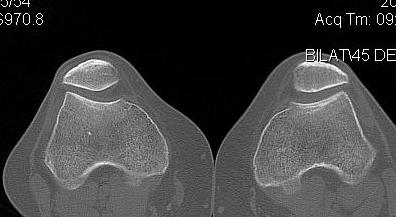

CT

1. Skyline View

Assess for

- lateral tilt

- subluxation

- trochlea dysplasia

2. Lateralisation of tibial tuberosity

Jones et al Skeletal Radiology

Superimpose 2 axial slices

A. Axial slice of trochlea

- line of posterior condyles

- line perpendicular through trochlea

B. Slice through tibial tuberosity

- perpendicular line through TT

Calculate Distance between two points / TTTG

10 - 15 mm normal, > 15 abnormal

Pandit et al Int Orthop 2011

- normal 10 +/-1 on MRI